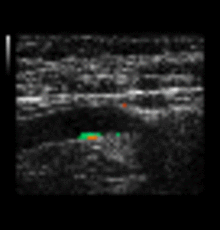

Schlaganfall-Check

In der Medizin wird immer wieder versucht, das Risiko für eine Schlaganfallgefährdung und allgemein für Gefäßerkrankungen zu messen.

Die IMT (Intima-Media-Dicke) hat, nach dem derzeitigen Stand der Wissenschaft, eine hohe Korrelation mit diesen Erkrankungen.

Ich führe eine Ultraschalluntersuchung der Halsschlagadern durch. Mit einem speziellen Computerprogramm kann die Dicke der inneren Gefäßwand in einer bislang nicht möglichen Genauigkeit vermessen werden. Kommt infrage für Risikogruppen: Menschen mit hohem Blutdruck, erhöhten Cholesterinwerten, Diabetiker, Raucher und Frauen, die die Pille nehmen. Für einen Schlaganfall gibt es kaum Warnsignale, deshalb sollten diese Personen ab dem 55. Lebensjahr alle 5 Jahre diese  Vorsorgemaßnahme durchführen lassen.